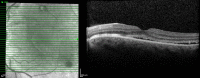

Central Serous Chorioretinopathy: Pathogenesis and Management

Central serous chorioretinopathy (CSC) is a common retina disease and has a relative high recurrence rate, etiology, and pathogenesis of which remains largely ambiguous. The effects on the retina are usually self-limited, although some people are left with permanent vision loss due to progressive and irreversible photoreceptor damage or retinal pigment epithelium atrophy. There have been a number of interventions used in CSC, including, but not limited to, laser treatment, photodynamic therapy (PDT), intravitreal injection of anti-vascular endothelial growth factor agents, and subthreshold lasers. It is not clear whether there is a clinically important benefit to treating acute CSC, which often resolves spontaneously as part of its natural history. Of the interventions studied to date, PDT and micropulse laser treatment appear the most promising. .